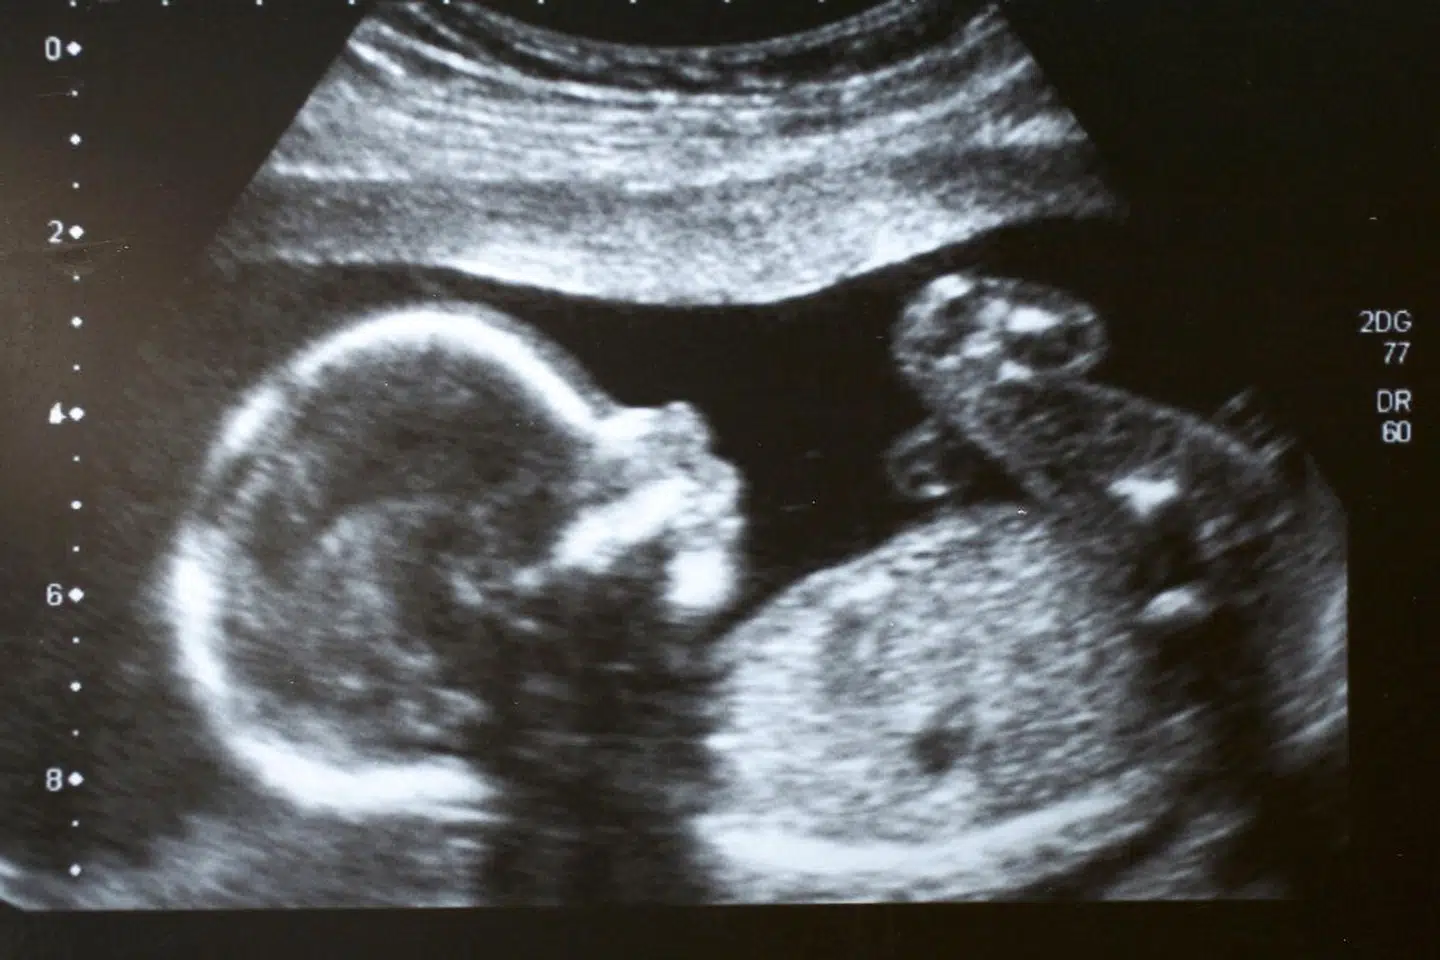

I sidste måned kunne kendisfrisøren Dennis Knudsen afsløre, at han var blevet singlefar. Sønnen Lucas kom til verden 17. juni på et hospital i USA efter det, som Dennis Knudsen beskriver som »20 års kamp« for at blive far.